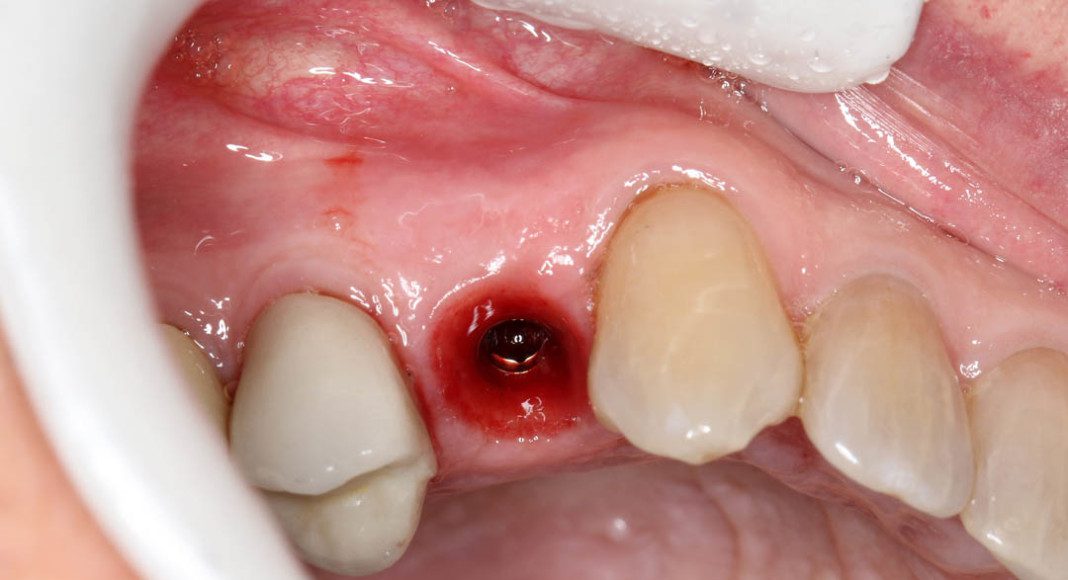

Though not obvious on the x-ray, this patient has fractured his upper right 1st premolar. Treatment plan: Extract tooth, place implant, fabricate an immediate, screw retained, temporary implant crown. Patient will never need to wear a removable partial or go without a tooth.